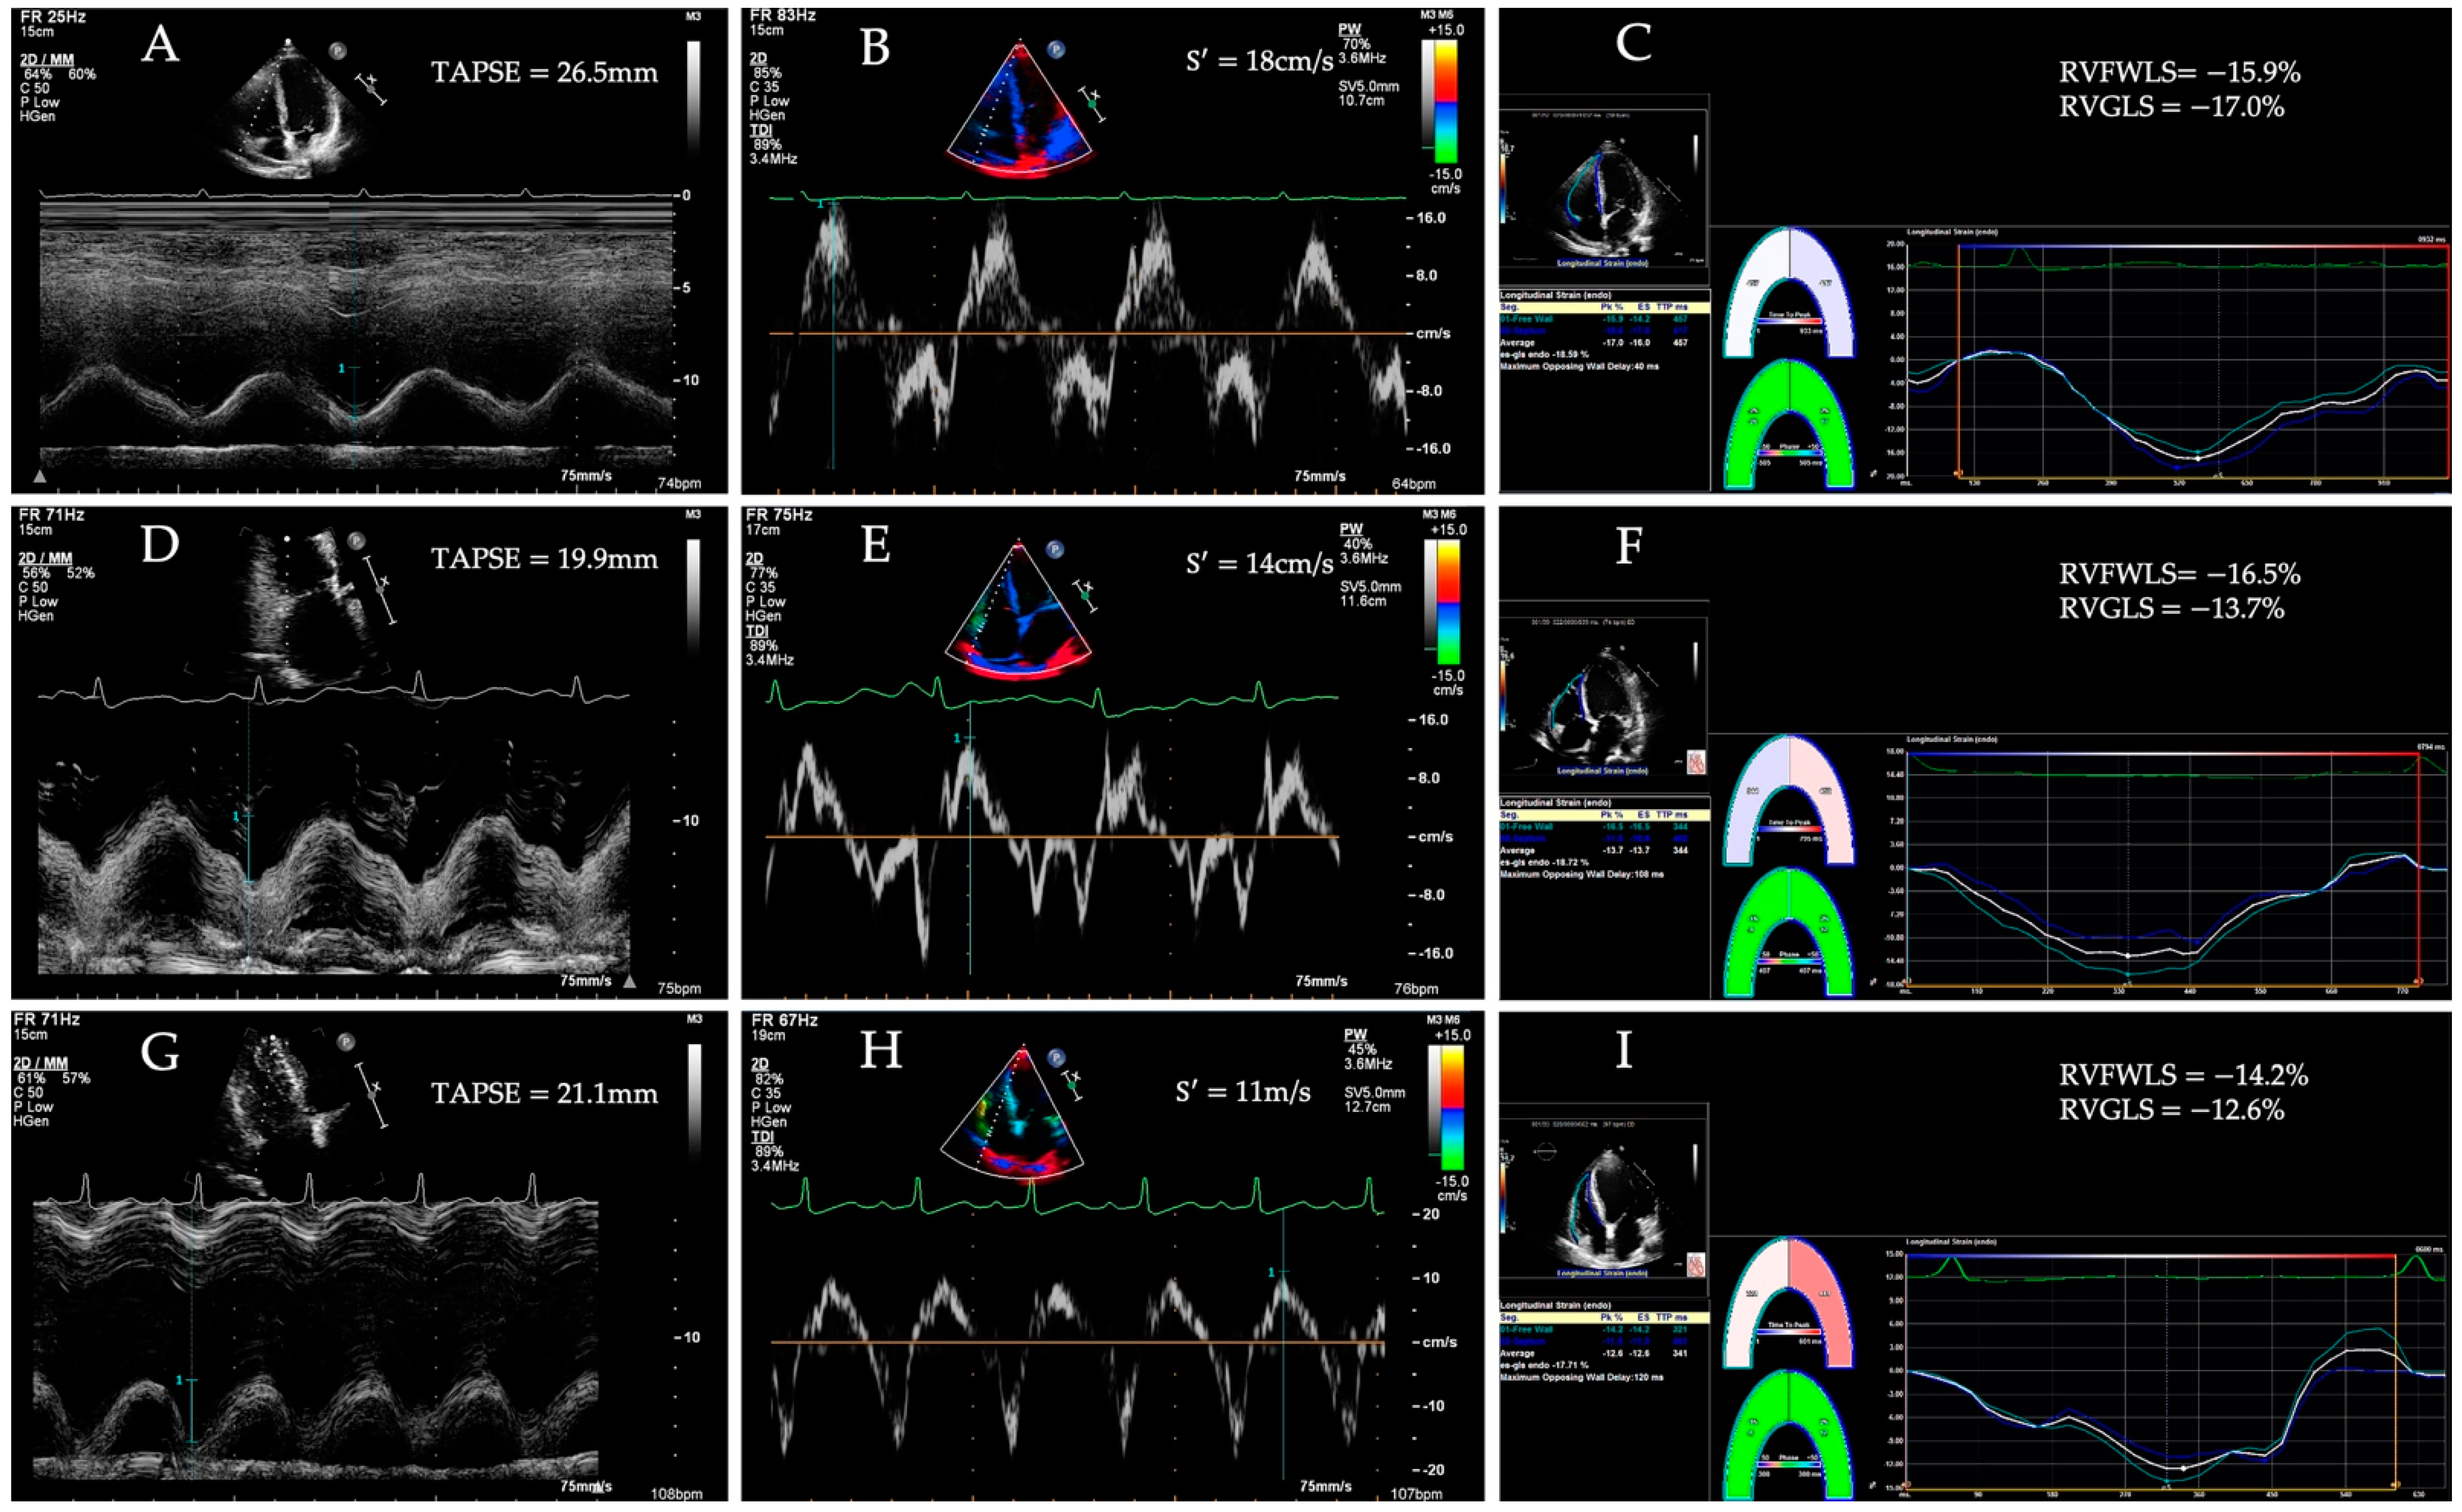

3.1. Tissue Doppler Imaging

3.2. Two-Dimensional Speckle Tracking Echocardiography

7. RV Longitudinal Strain in HF Patients with Preserved Traditional RV Function Parameters

- Morris, D.A.; Krisper, M.; Nakatani, S.; Koehncke, C.; Otsuji, Y.; Belyavskiy, E.; Krishnan, A.K.R.; Kropf, M.; Osmanoglou, E.; Boldt, L.-H.; et al. Normal range and usefulness of right ventricular systolic strain to detect subtle right ventricular systolic abnormalities in patients with heart failure: A multicentre study. Eur. Heart J. Cardiovasc. Imaging 2017, 18, 212–223. [Google Scholar] [CrossRef] [Green Version]